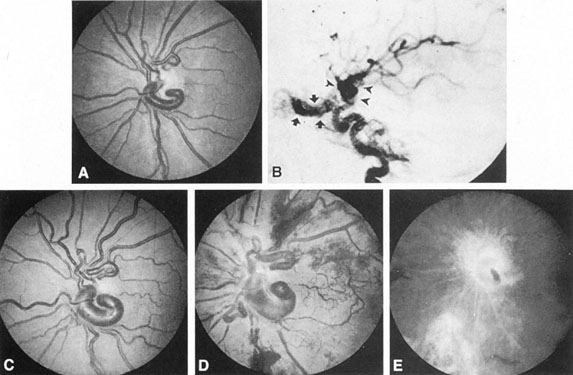

Fig. 7. Supratentorial arteriovenous malformation in a 28-year-old woman with a history of focal motor seizures for many years and a recent subarachnoid hemorrhage. A: Lateral projection carotid arteriogram demonstrating a huge deep hemispheral arteriovenous malformation. B: Frontal projection. C: Fundus photograph showing anomalous tortuous vasculature in each eye. No retinal arteriovenous shunt was detectable.

From 85% to 90% of AVMs are in the supratentorial compartment and are supplied primarily by the carotid circulation (Figs. 7 and 8). The remainder are supplied by the vertebrobasilar system. The approximate frequency of location is as follows: frontal, 22%; temporal, 18%; parietal, 27%; occipital, 5%; and deep intraventricular or paraventricular, 18%. The intracerebral site of the malformation does not necessarily indicate that there will be signs referable to that area simply from the mass effect of the malformation. Clinical features primarily result from subarachnoid hemorrhage or intraparenchymal hemorrhage with hematoma formation.

SUPRATENTORIAL